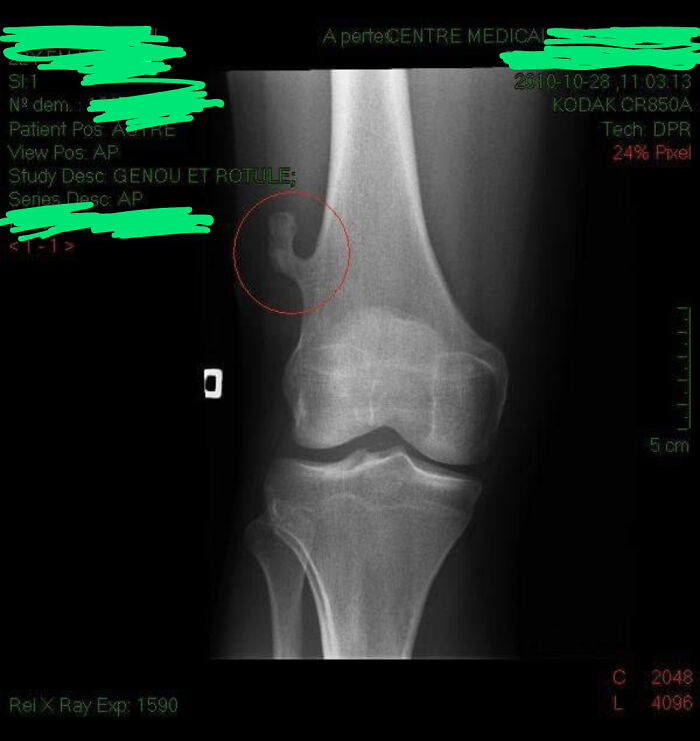

I Just Found My X-Ray From 2010. It Shows An Abnormal Bone Growth On My Right Femur That Has Since Been Surgically Removed